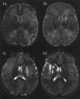

Hemiparesis, or unilateral paresis, is weakness of one entire side of the body (hemi- means "half"). Hemiplegia is, in its most severe form, complete paralysis of half of the body. [Source: Wikipedia ]